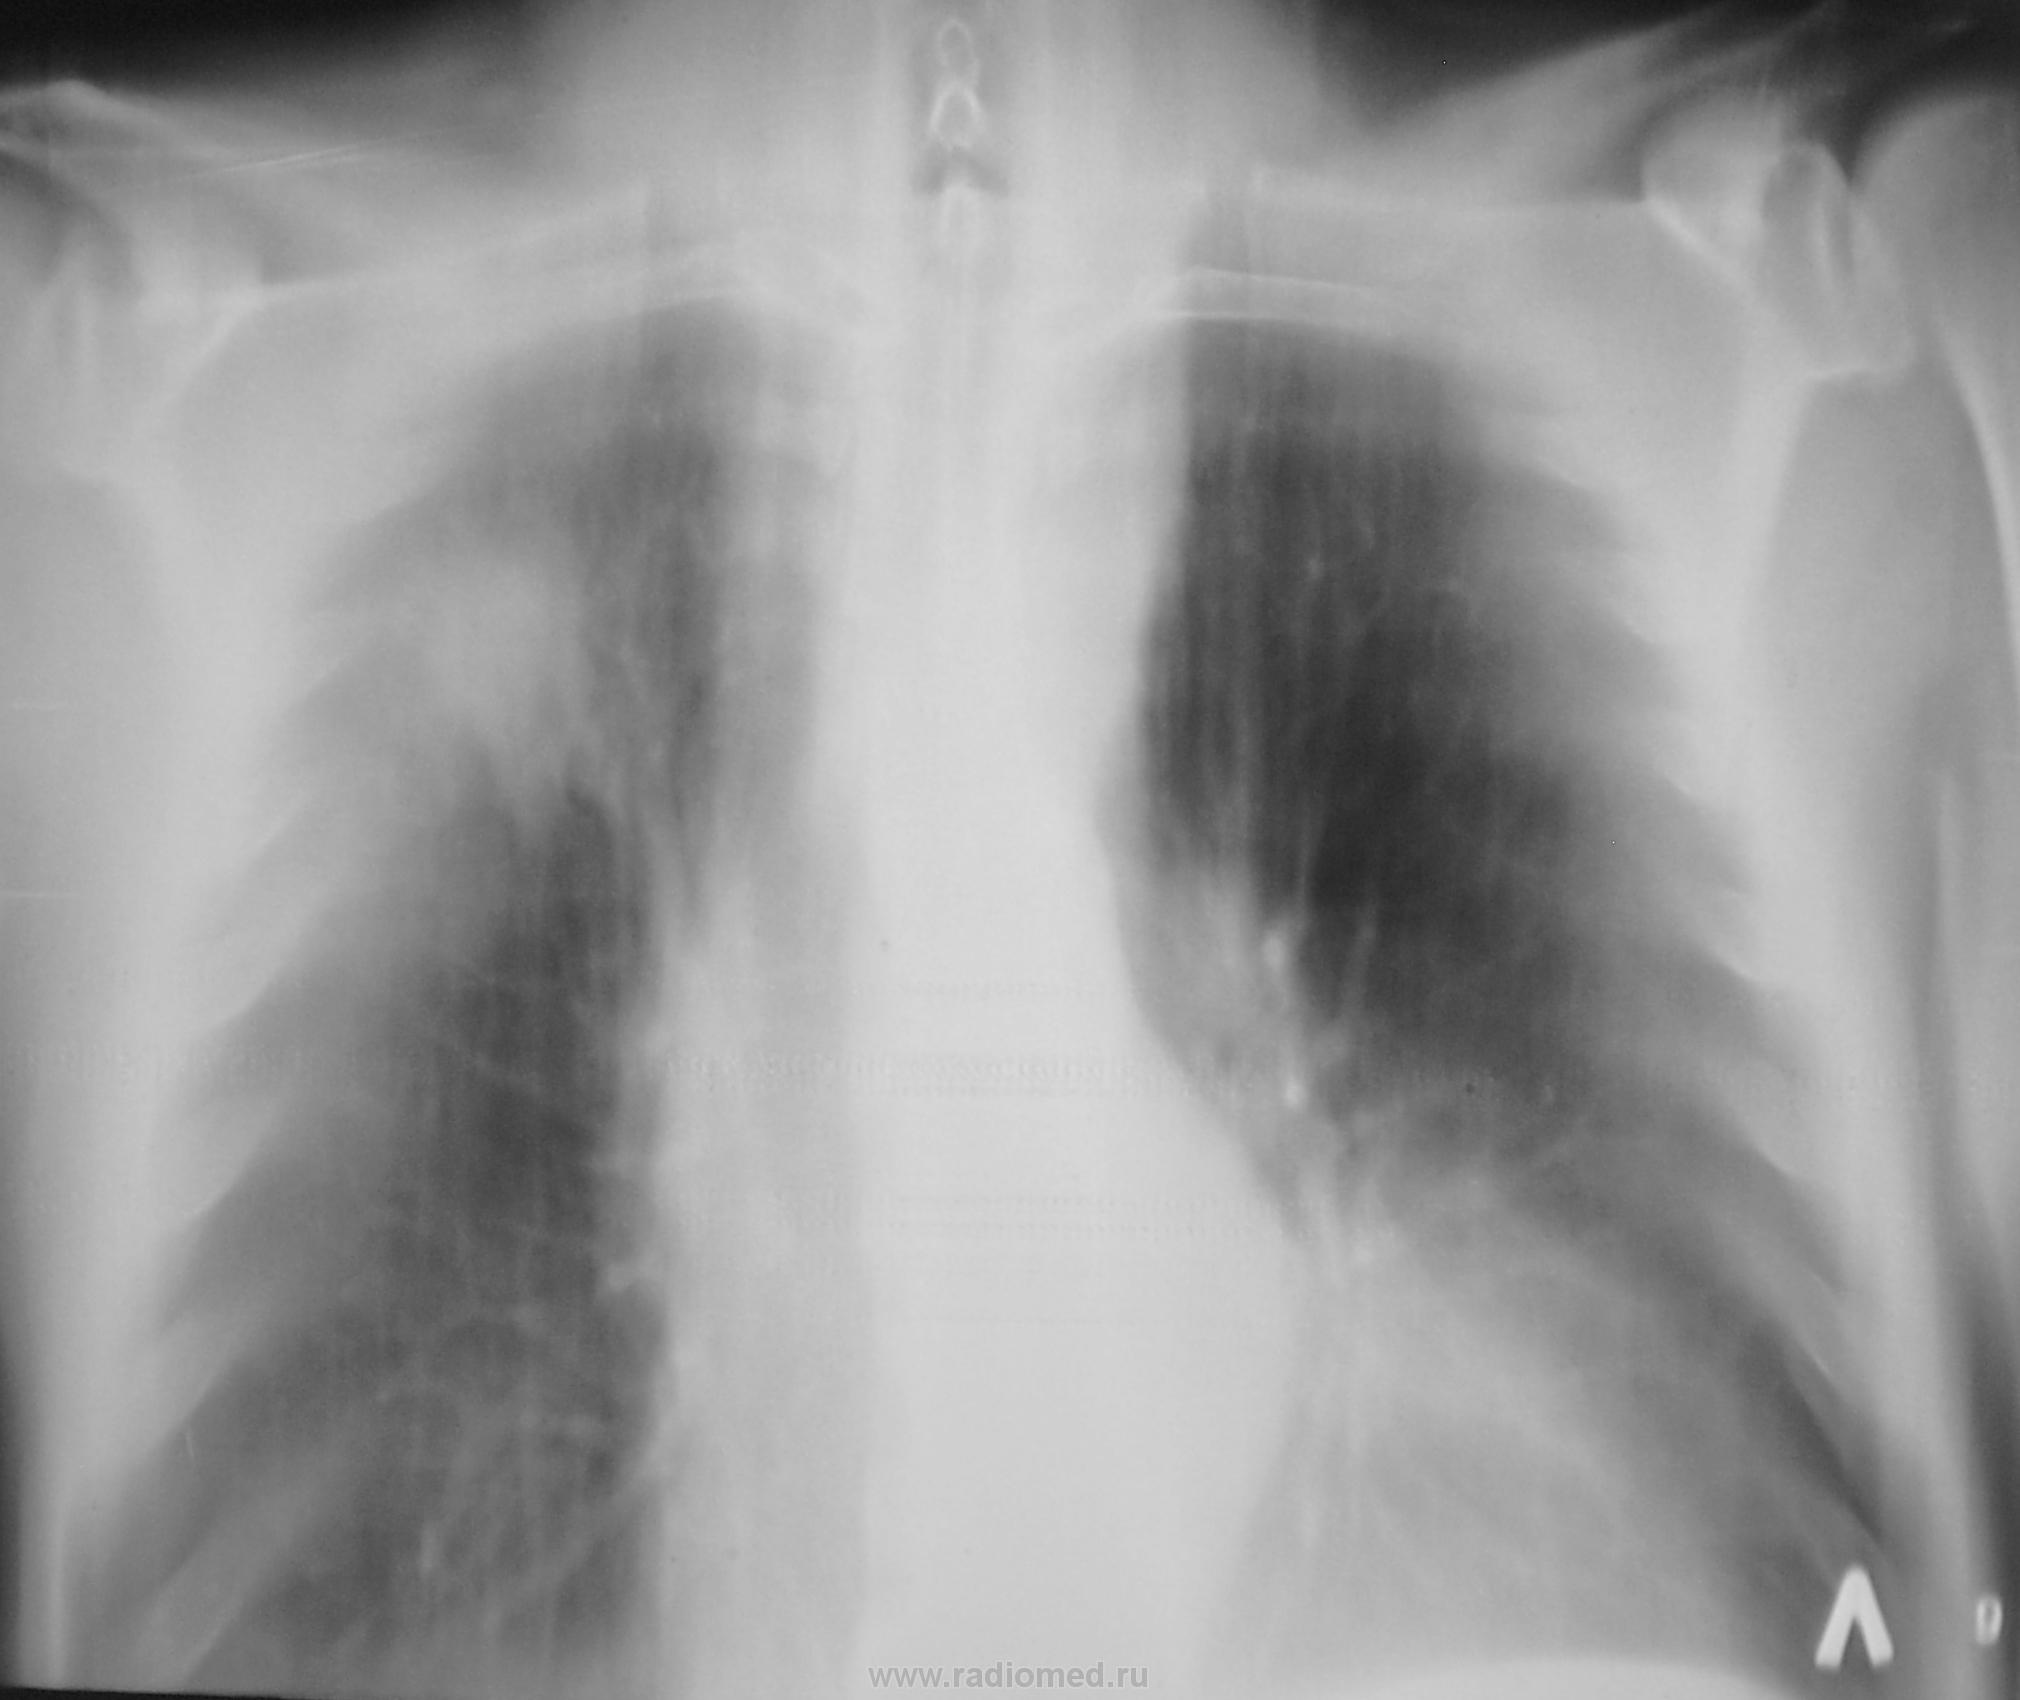

После "флюшки" сделали рентгенограмму. Какие будут мнения?

Инфильтрат во II-ом межреберье справа(S2).

определяется округлая тень с неровными контурами. Возраст пациента, жалобы и желательно боковой. Кстати в проекции 1 и 2-ого рёбер, тоже очаги? Лёгочный рисунок деформирован за счёт пневмофиброзных изменений.

И опять его Величество? На фоне пневмофиброза и выраженного сосудистого компонента.

И на него в том числе. Очень не нравится легочной рисунок, диффузно усилен, несколько деформирован. А справа в S6 тоже не все гладко. На первое-ТВС, на второе-периферия или МTS.

посылать пациента к фтизиатру. Я бы его отправил к онкологу, так как очерченный фрагмет расцениваю как гиповентиляцию. Вышележащая тень - опухоль. Жду другие мнения. Сегодня интересный вечер для совместного обсуждения клинических наблюдений.

Да, профилактическая. Из жалоб кашель, который связывается с курением.

Похоже на с-r с mts в ЛУ средостения и гиповентиляцией верхней доли.